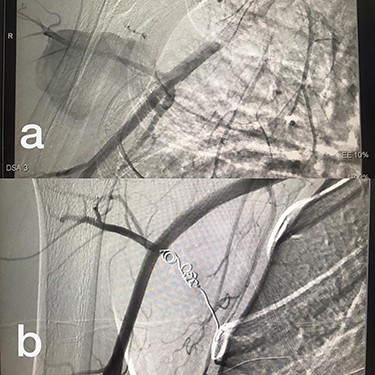

Sites of injury included 6 Posterior Tibialis arteries (27.2%) (Fig. 1), 2 deep femoral arteries (9.09%), 2 Superficial femoral arteries (9.09%) and 2 maxillary arteries (9.09%). We had only one injured artery (4.54%) in each of the following sites: internal pudendal a., Axillary a. (Fig. 2), Proneal a., Lumbar a., External carotid a., Anterior Tibialis a., common iliac a. (Fig. 3), temporal a., Thoracic aorta and Internal iliac artery (Fig. 4).

(a) Internal iliac artery before intervention, (b and c) after coil embolization.